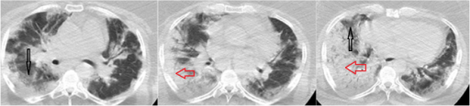

a-f) Chest computed tomography and histologic findings of viral pneumonia